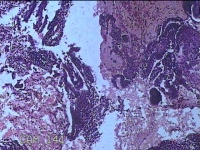

子宫腔内膜组织

性别

女

年龄

44岁

临床诊断

子宫异常出血、甲亢、轻度贫血

一般病史

阴道流血20天,加重1天。

标本名称

大体所见

灰白暗红色不规则碎组织3x2.8x0.3cm一堆。

貌似增生反应子宫内膜。